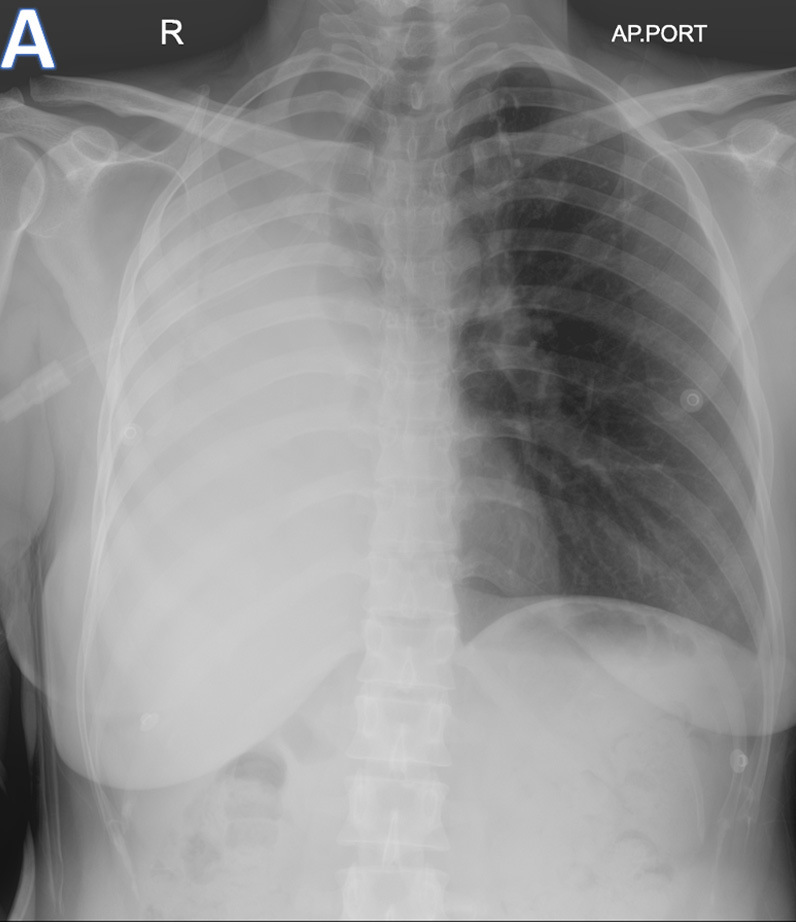

D – Axial CT Thorax

• ARROW:  Isodense mass lesion with peripheral calcific specks and endobronchial extension.

• STAR: Organised / Clotted - Hemorrhagic contents in the right hemithorax.